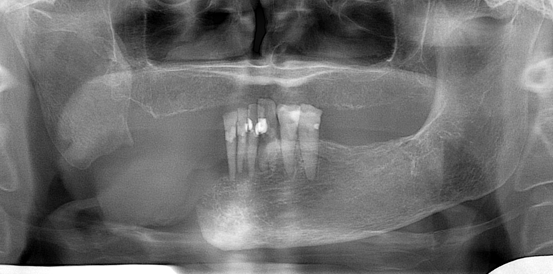

Lower Jaw Defects

Fortunately, they are less common now that combined chemo/radiation therapy has become the primary treatment modality for large cancers of the tongue, tonsils, and throat.  The main etiologies are: tumors of the lower jaw, ostreoradionecrosis and trauma.  Small defects can be relatively easy to treat.  Large continuity defects require a sophisticated multidisciplinary surgical and restorative/rehabilitative treatment teams.

Oral Cancer (obturator prosthesis)